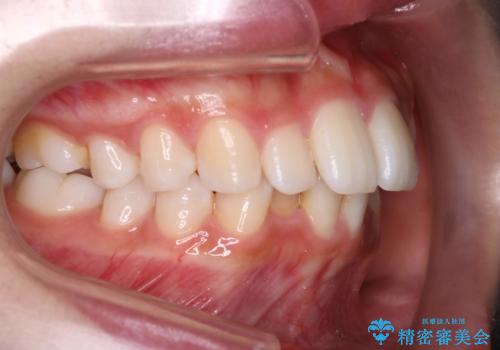

Invisalign インビザラインによる軽度なガタつきの改善

- 奥歯の位置関係はそこまで大きくいじらず、前歯群のみでガタつきの改善を計画しました

奥歯の位置関係に改善の余地はありますが、機能的に問題のない cusp to fossa の関係で咬めているため、前歯のガタつきを前歯のみで改善するというシンプルな計画で、短期間で治療を終了させました。